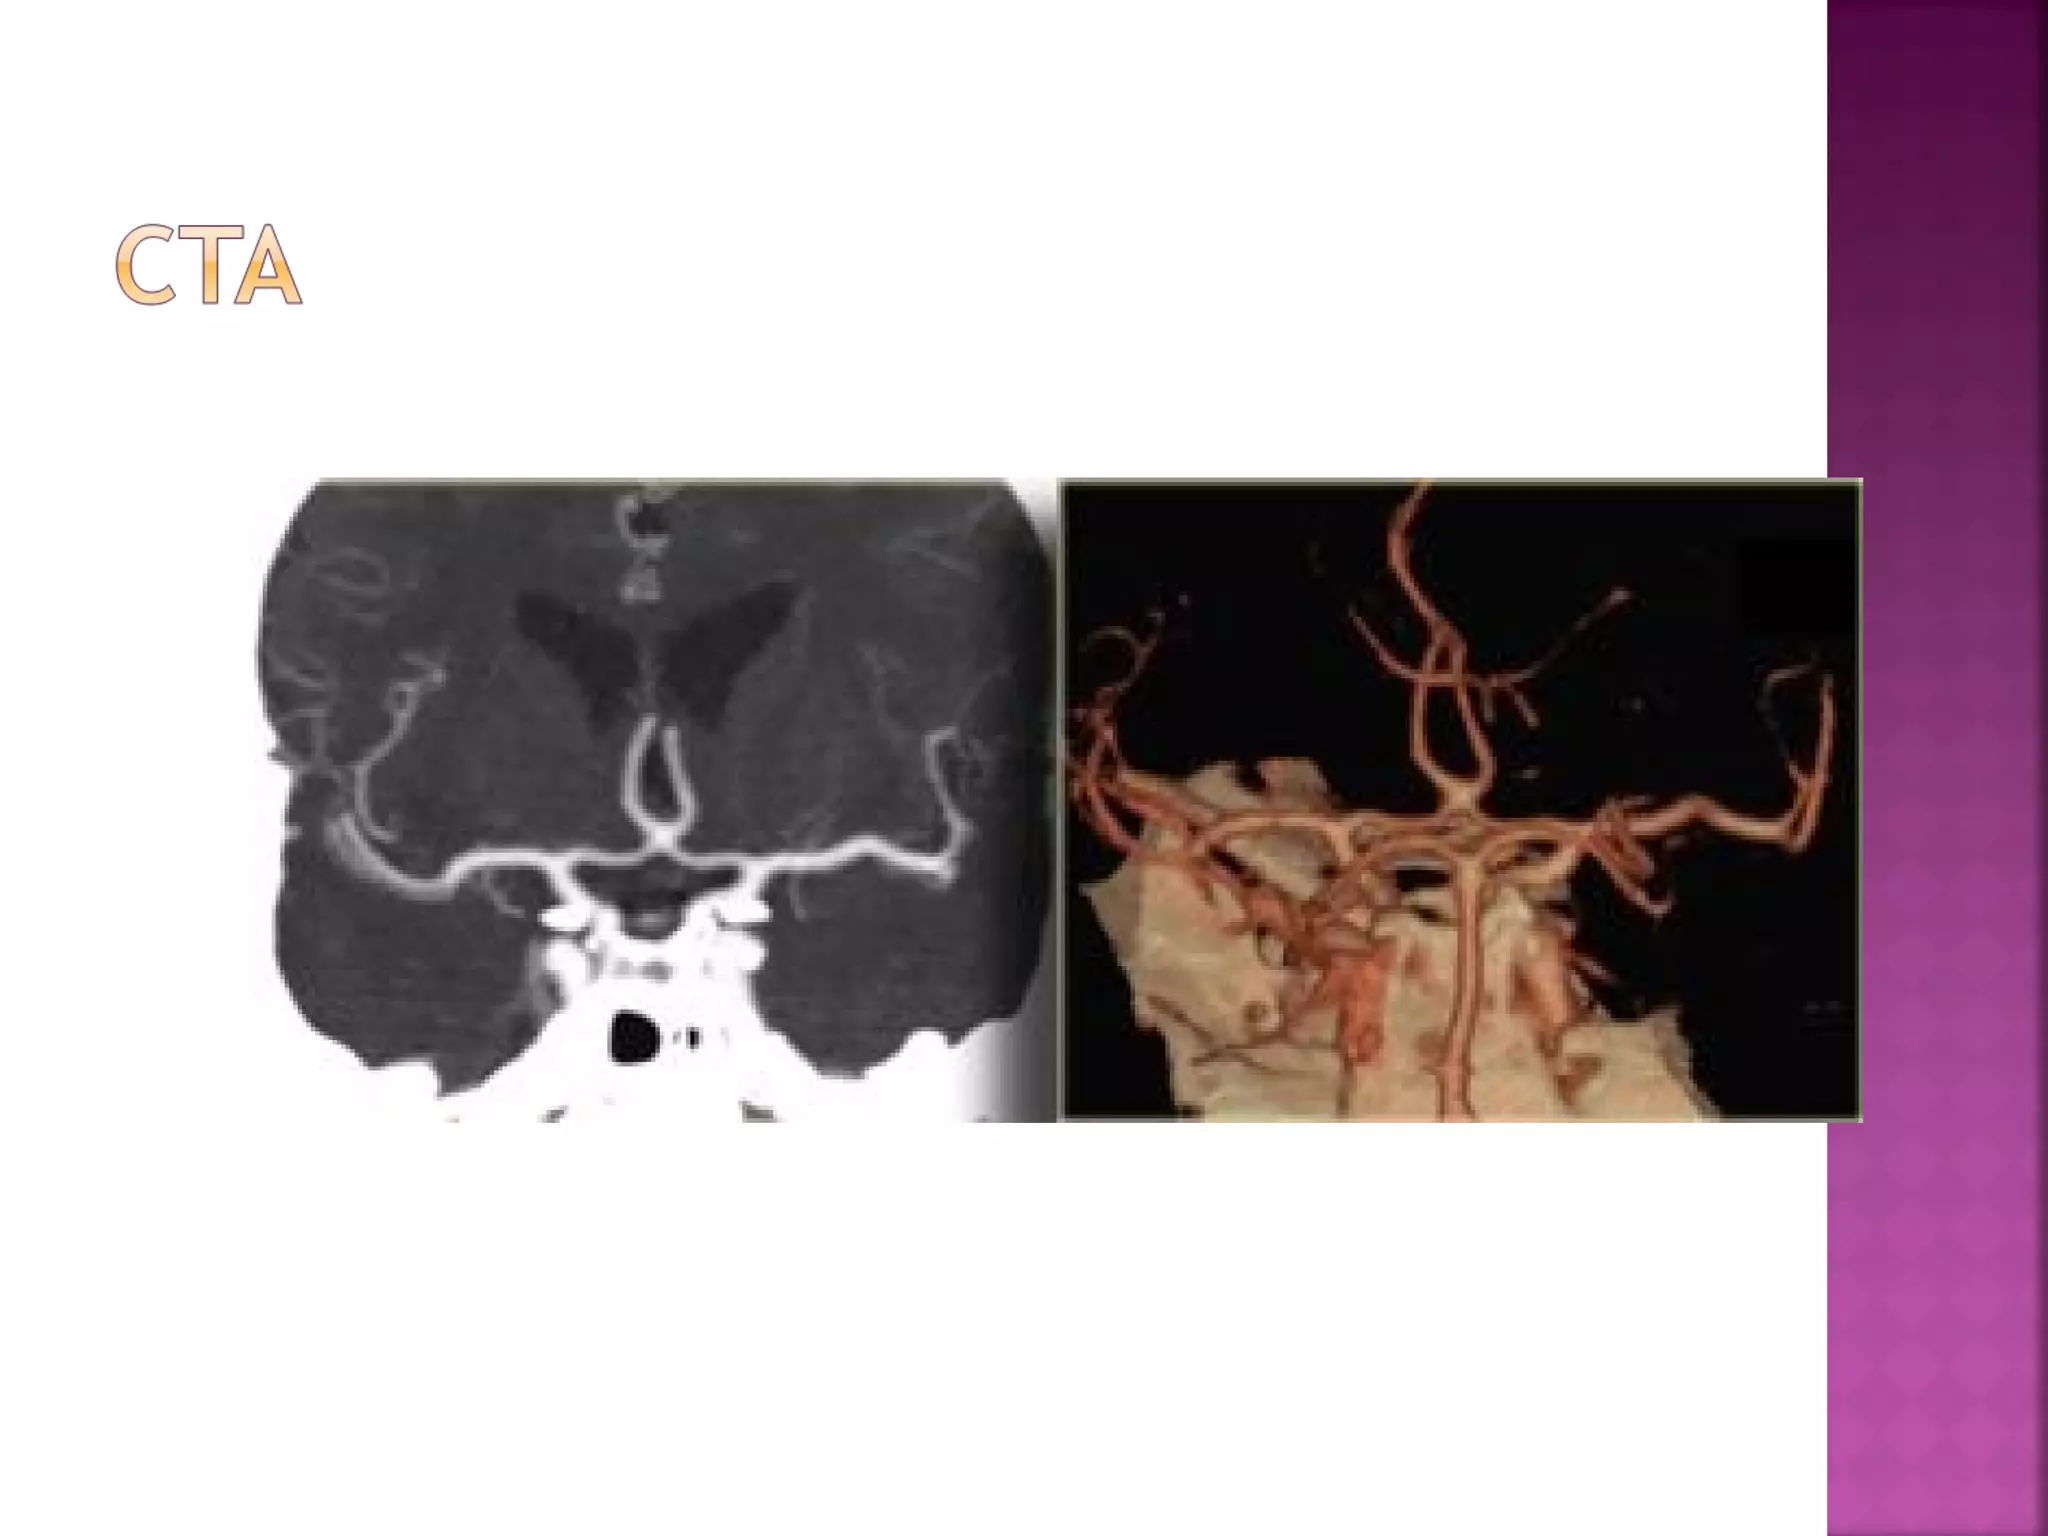

The goal ofimaging in a patient with acute stroke is:  Exclude hemorrhage  Differentiate between irreversibly affected brain tissue and reversibly impaired tissue (dead tissue versus tissue at risk)  Identify stenosis or occlusion of major extraand intracranial arteries

 This is aresult of thrombus or embolus in the MCA.